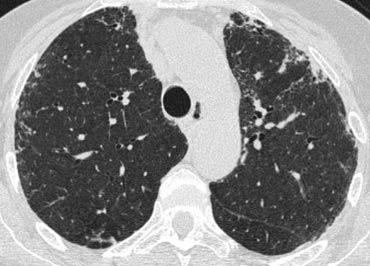

Bên trái là một trường hợp khác của UIP.

Sự chiếm ưu thế ở vùng phổi dưới được thể hiện khi bạn cuộn qua các hình ảnh.

Lưu ý độ mờ kính mài ở thùy dưới phổi trái do mô xơ thay thế không khí trong các phế nang.

Trường hợp bên trái cho thấy các nang tổ ong dưới màng phổi ở nhiều lớp liên tiếp.

Ngoài ra còn có sự chiếm ưu thế ở thùy dưới và giãn phế quản do co kéo lan rộng.

Những phát hiện này điển hình cho Viêm phổi Mô kẽ Thông thường (UIP).

UIP hay ‘phổi giai đoạn cuối’ là một chẩn đoán bệnh lý và thường được xác định qua sinh thiết phổi, khi hình ảnh tổ ong có thể nhìn thấy được.

Xơ phổi vô căn (IPF) chiếm hơn 60% các trường hợp UIP.

UIP kèm xơ hóa phổi cũng là một dạng tổn thương phổ biến trong bệnh tự miễn và tổn thương phổi do thuốc.

Nhiều loại thuốc đã được xác định có liên quan, nhưng dạng tổn thương này thường gặp nhất là do các thuốc hóa trị liệu gây độc tế bào như bleomycin, busulfan, vincristine, methotrexate, adriamycin và carmustine (BCNU).